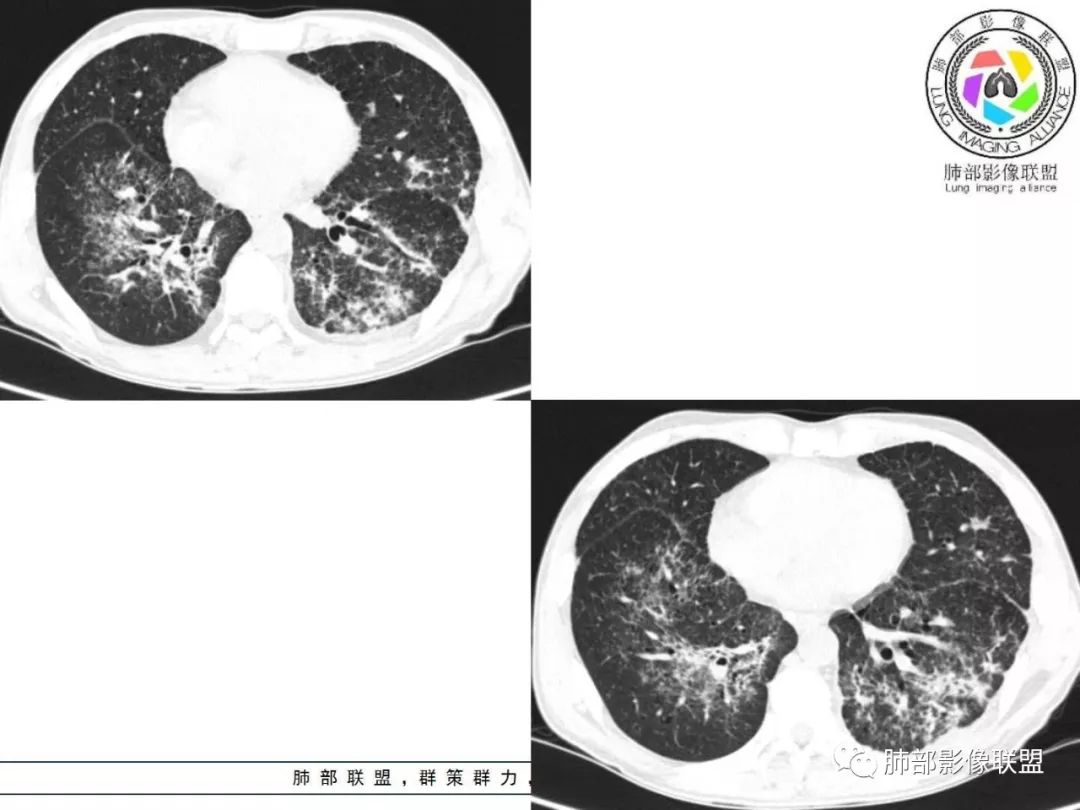

胸部CT:两肺弥漫病灶,磨玻璃影,少许实变,部分累及胸膜,磨玻璃区可见囊?少许胸腔积液,两肺可见结节,支气管血管束增粗,小叶间隔增厚,支气管走形有扭曲扩张,可见纤维化。气肿、大泡。考虑:感染性病变,PCP?查下HIV,CD4,G等。鉴别结核、结缔组织病肺浸润。

两肺弥漫性病变,沿支气管血管束分布,部分细支气管轻度扩张,两上中肺为主,部分累及胸膜下,部分磨玻璃影,部分纤维化,肺气肿肺大疱背景,胸膜增厚,少量积液,考虑结核可能性大,鉴别op、LIP,PCP纤维化

中老年男性,发热1月余,双肺弥漫性病变,多发网格、结节、斑片状实变影及磨玻璃影,胸膜下及中轴间质都受累,支气管血管束增粗、变形,支气管扩张,叶间裂及小叶间隔增厚,整体间质性改变明显,考虑结核?OP、LIP?进一步除外PCP、肿瘤、结节病等。

中老年男性,发热时间长,有高热,血沉不快,双肺弥漫性病变,多发网格、结节、斑片状实变影及磨玻璃影,胸膜下、中轴间质及小叶间隔增厚,支气管血管束增粗、变形,牵拉性支气管扩张,叶间裂及小叶间隔增厚,第一考虑弥漫性间质病变,炎症?结核?结节病?综合考虑,结核排前面,多形态,病程长,间质增厚明显,较一般感染硬结感强。不确定的地方在,病灶范围广,间质累及严重,而且病人高热。其次考虑感染,或特殊菌感染。结节病不除外。

病灶呈片状磨玻璃密度影,呈典型的烟花征。磨玻璃影密度偏高,有网结节样改变,与正常肺实质分界清楚,且常见相对高密度的勾画。

烟花征分为3肿类型:晕征、反晕征及均匀分布。

临床中毒症状常较轻,病变相对稳定,增强扫描常无异常强化。

2. 肺气肿背景(小叶中心性肺气肿);双肺多发病灶整体沿血管支气管束及胸膜下分布,以上叶及下叶背段分布为主,有实变及GGO,边界清楚,有树芽,小叶间隔及中央间质增厚,叶间裂见到多发结节,部分支气管不规则牵拉扩张,提示病灶纤维化明显,结合临床病史,考虑病灶为间质性感染,肺门及纵隔内有钙化淋巴结,小叶间隔结节,考虑淋巴道增值性疾病可能,综合常规要怀疑间质性肺结核。

3. 该病例临床提示感染,有支气管扩张,提示纤维化,需要与感染后的OP鉴别,但是OP病灶常无结节感;间质性肺结核有时与不典型结节病鉴别也比较困难,结节病常以双肺门淋巴结增大为特征。临床上结核发病率较高。